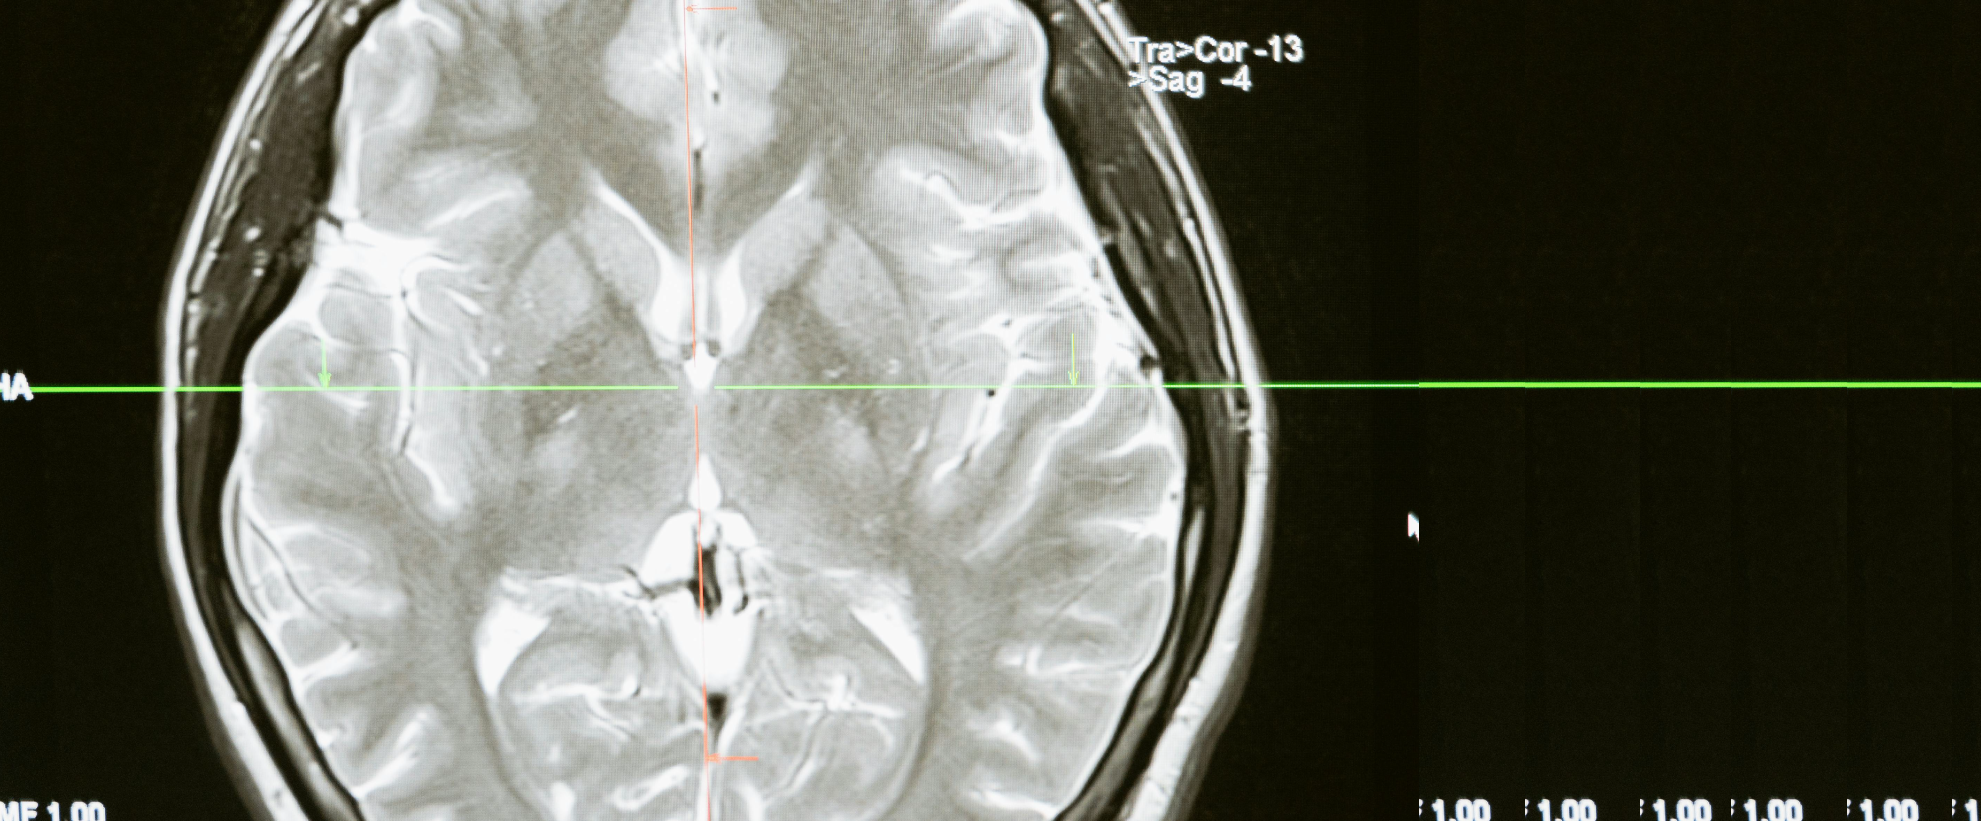

Mars 2025 : Imagerie médicale, les dessous numériques d'une histoire physique (Nicolas Passat, CRESTIC) : lien

Mars 2025 : Apnée du sommeil, rencontre entre corps et cortex (Apolline Durtette, C2S) : lien